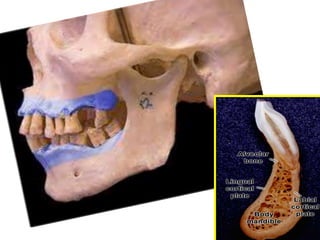

adult alveolar process is composed of 2 parts:

1)supporting bone (cortical & spongy).

2) alveolar bone proper.

Recently component of alveolar process described as follow:

1) facial & lingual cortical plates: which are compact bone.

2)central spongiosa: its spongy bone fills the space between

cortical plates & alveolar bone

3) alveolar bone : from inner side facing P.D.L .

N.b: alveolar bone & cortical plate merges at alveolar

process crest (1.5 to 2mm below the level of C.E.J)

Macro-anatomy

Alveolar

bone

proper

Supporting

Inner

&outer

cortical

plates

spongiosa

ALVEOLAR PROCESS